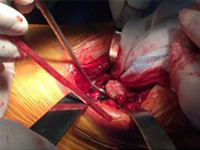

張某,男,50歲,因“左股骨骨不連”入院。植骨+PRP治療后8月完全愈合。

術(shù)后完全愈合

03.jpg